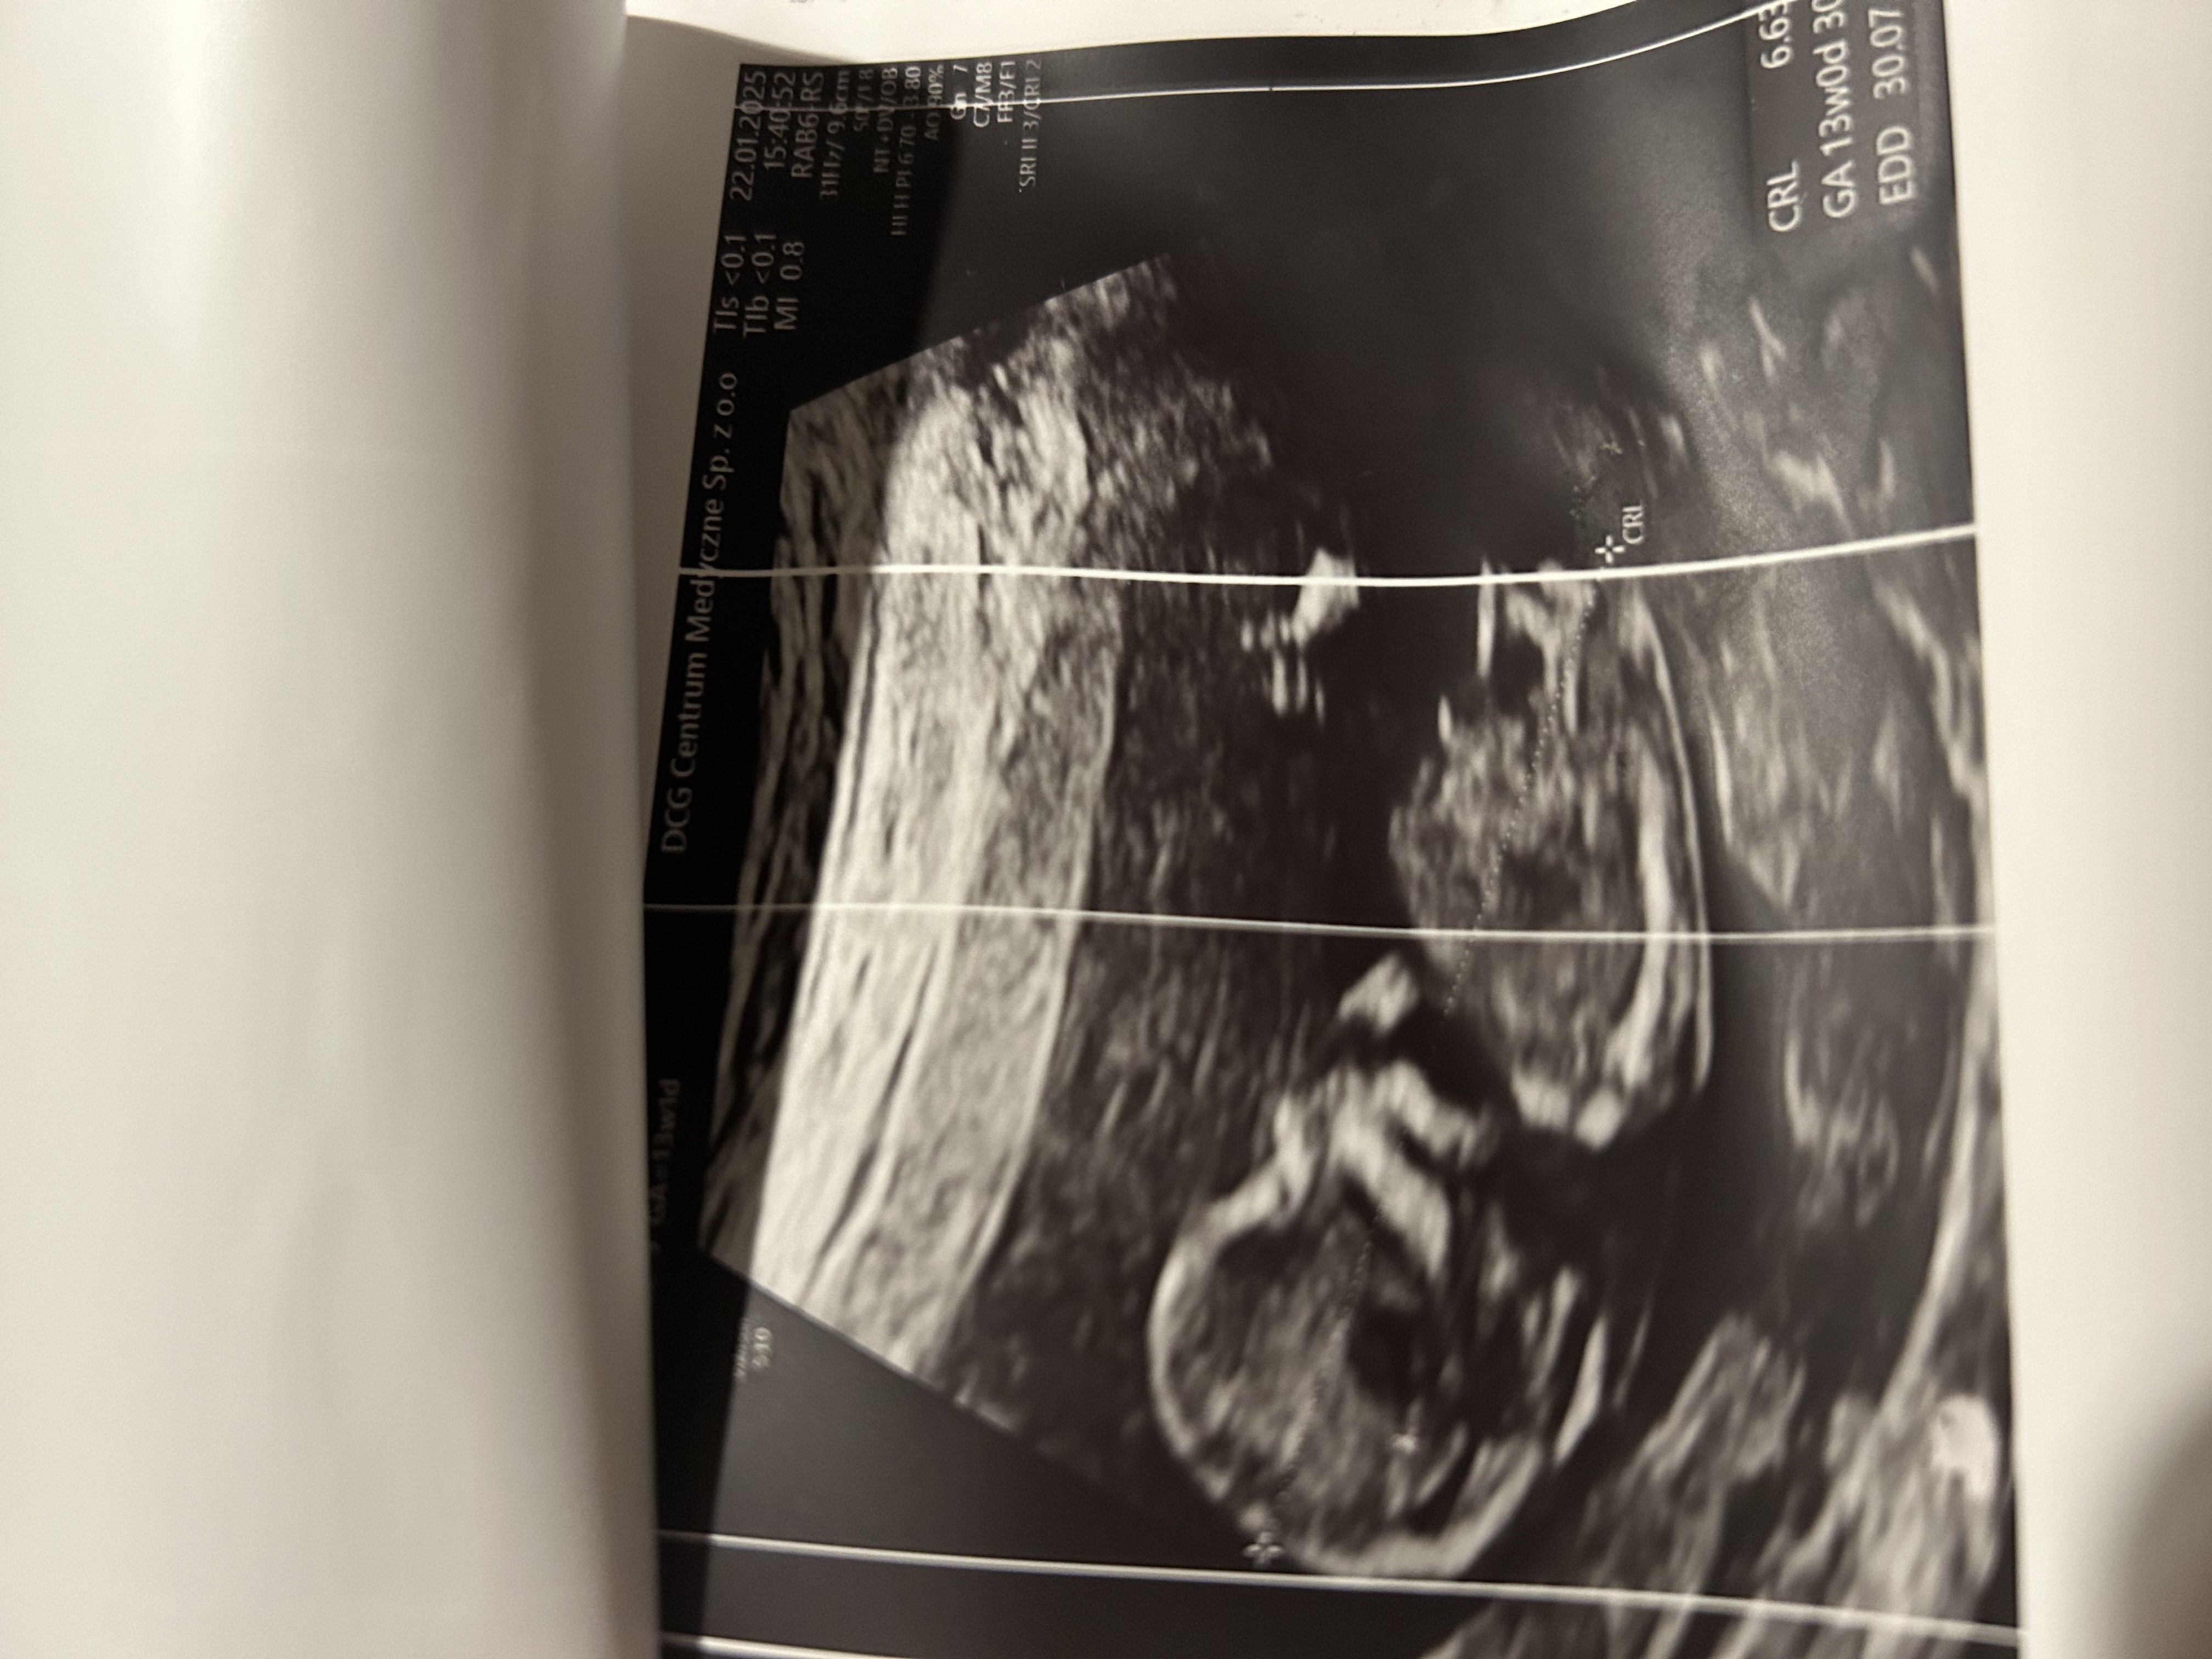

Hej jestem po badaniach prenatalnych. Czy widać waszym zdaniem już płeć u dzidziusia?

To skoro masz info od lekarza to po co pytasz randomy w necie?Widzial ale jestem ciekawa czy ktoś się zna i może potwierdzić![]()

Lekarz zasugerował dziewczynkę jestem bardzo szczęśliwa z tegoDokładnie